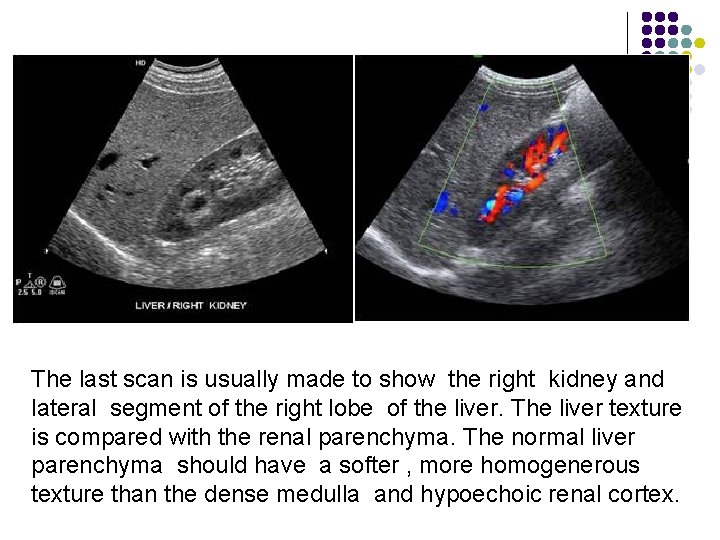

Longitudinal Scan Plane l Scan Ⅳ, Ⅴ, Ⅵ The nest three scans should be made in small increment through the right lobe of the liver. The last scan is usually made to show the right kidney and lateral segment of the right lobe of the liver. The liver texture is compared with the renal parenchyma. The normal liver parenchyma should have a softer , more homogenerous texture than the dense medulla and hypoechoic renal cortex. Liver size may be measured from the tip of the liver to the diaphragm. Generally this measurement is less than 15 cm, with 15 to 20 cm representing the upper limits of normal. Hepatomegaly is present when the liver measurement exceed 20 cm.

The last scan is usually made to show the right kidney and lateral segment of the right lobe of the liver. The liver texture is compared with the renal parenchyma. The normal liver parenchyma should have a softer , more homogenerous texture than the dense medulla and hypoechoic renal cortex.